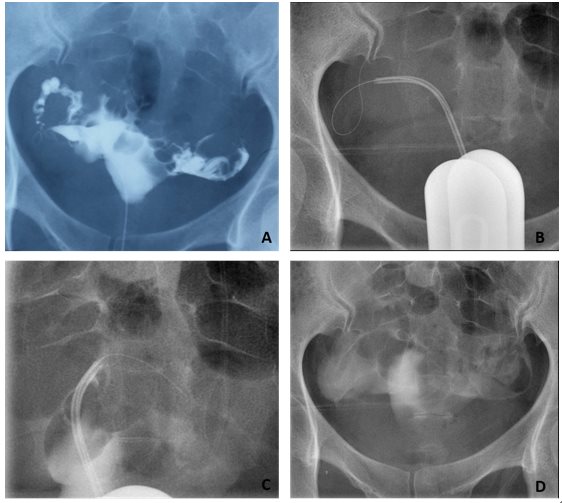

清华长庚医院5月3日电(通讯员 董鸿鹏)不孕症是妇科常见的一种疾病,严重困扰着有生育要求的妇女。女性不孕的主要有输卵管不孕,卵巢性不孕,子宫性不孕,免疫性不孕,内分泌性不孕等。如果输卵管有炎症,导致输卵管堵塞,精子不能通过与卵子相遇造成的不孕,则称为输卵管阻塞性不孕。据统计,输卵管阻塞性不孕占到女性不孕的1/3。 所以对不孕症患者进行输卵管通畅性检查和再通治疗也就显得非常重要和必不可少了。近日,放射科成功开展子宫输卵管造影及输卵管再通术。一位29岁女性患者因不孕来我院“影像介入门诊”就诊,放射科马永强医师调阅患者外院子宫输卵管造影检查资料,发现患者双侧输卵管堵塞积水(图A)。完善术前检查和准备后,马永强医师在透视引导下成功对患者双侧输卵管用微导丝实施了再通手术和药物通液治疗(图B、图C),术后造影提示双侧输卵管再通,造影剂经双侧输卵管伞端弥散进入腹腔良好(图D)。